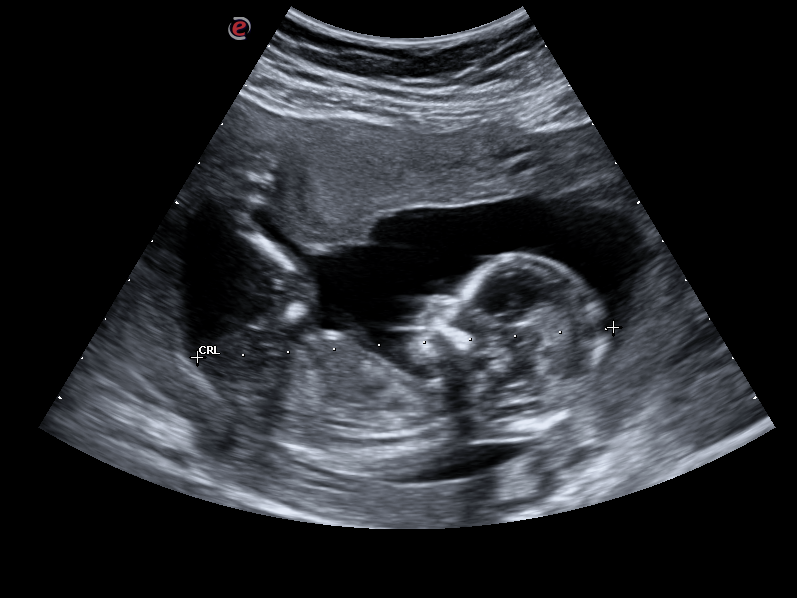

Anomaly/Detailed or morphological Ultrasound

(Please not this is not a 4D scan but a detailed 2D scan)

Preferably done at 18-24 weeks, but can be done later if the gestation was missed.

A detailed ultrasound scan that looks at your baby’s body and organs but also observes the position of the placenta, the umbilical cord, the amniotic fluid.

We will check to see if your baby has any abnormalities in their growth or development, including in their brain, face, heart, spine, stomach, kidneys bladder and limbs. Some of the abnormalities we aim to exclude are a cleft lip, spina bifida, a “hole” in the fetal heart, club feet ect.

This type of scan is very important check that your baby is healthy. I value this scan the most important ultrasound in your pregnancy.